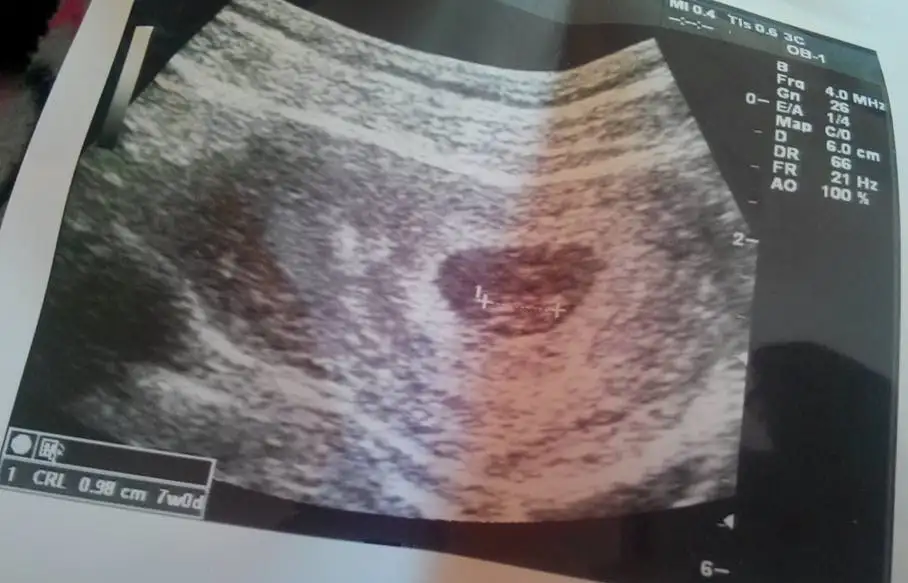

Merhaba arkadaşlar.. Herkes sağlıkla alsın inşallah bebişini kucağına.. 7. Haftadayım bende. 6+3 fotosuna göre sizce neye benziyor :)

Eklentiler

• image.webp

image.webp

19,2 KB · Görüntüleme: 171